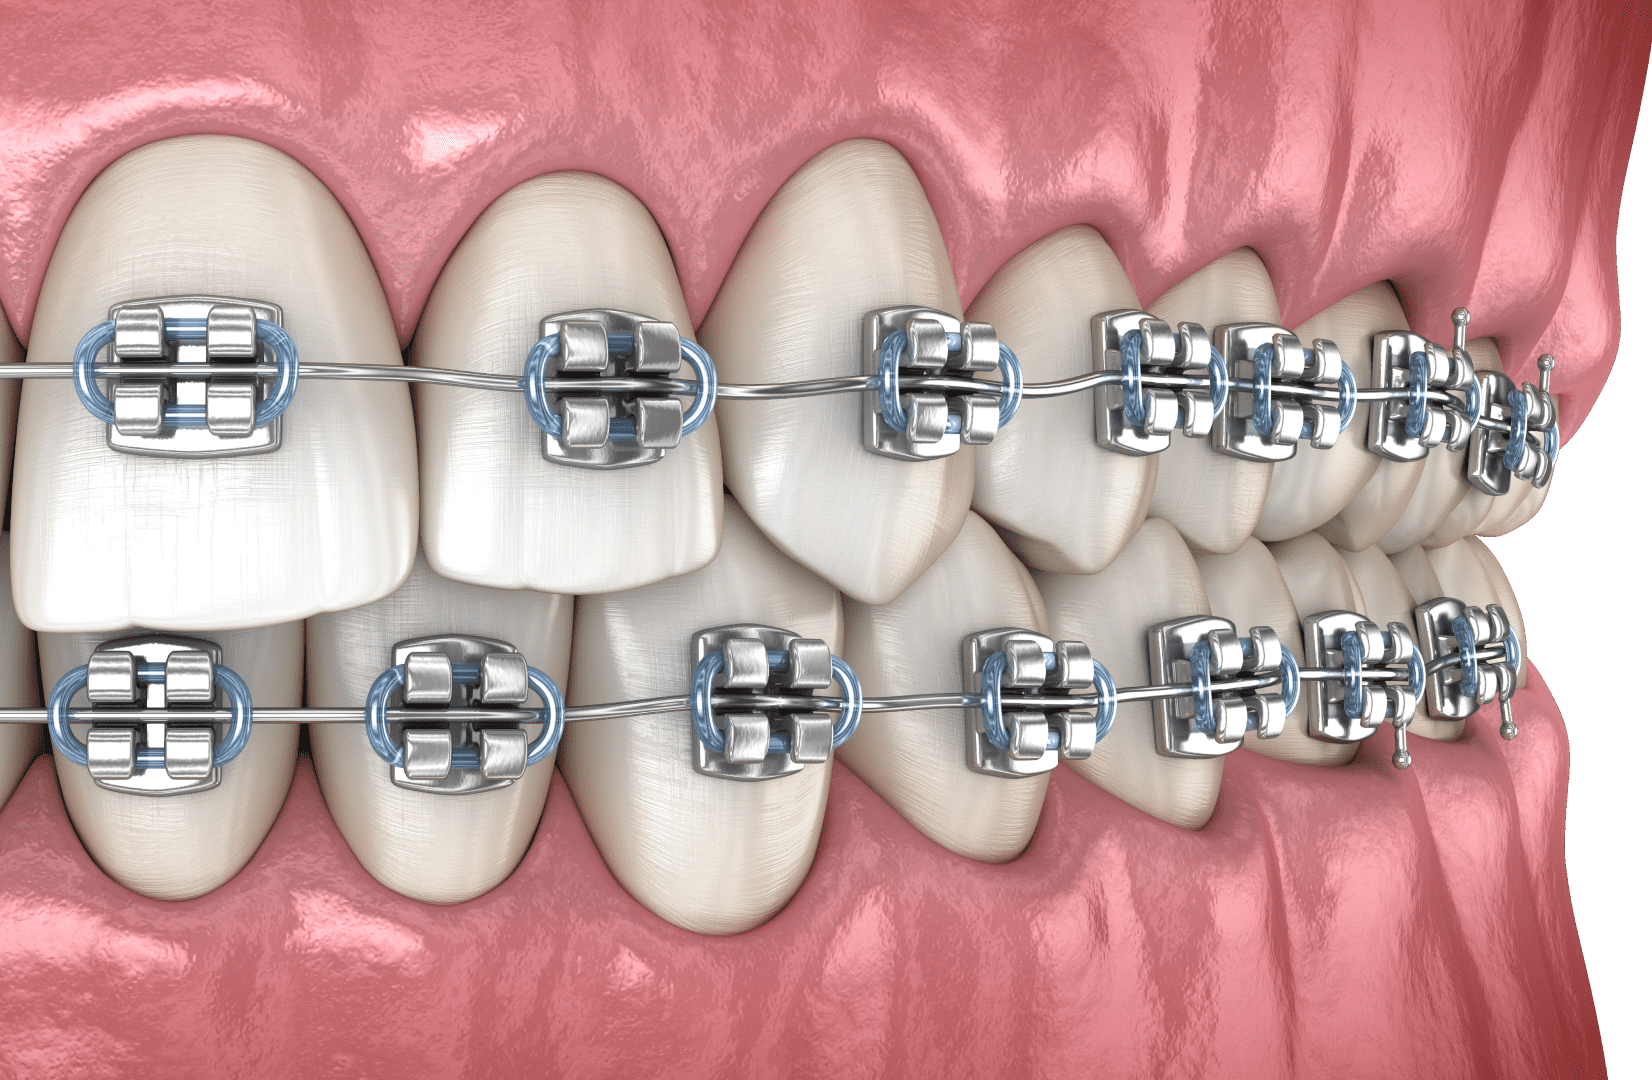

Брекети

Брекет-система — це найефективніший метод вирівнювання зубів різної складності. Класичний апарат (самолігуючі брекети) складається з маленьких замочків, які кріпляться на кожен зуб і фіксують у пазах металеву дугу. Лігатурна конструкція включає також еластичні резинки або кільця з дроту.

Вирівнювання зубного ряду відбувається за рахунок натягнутої, як пружина, дуги, яка, прагнучи повернутися в початкове положення, чинить тиск на зуби та зміщує їх за собою.

Переваги:

- висока ефективність, зокрема в складних клінічних випадках;

- застосовується і для дітей, і для дорослих;

- широкий вибір конструкцій, завдяки чому кожен пацієнт може підібрати для себе оптимальний варіант за ціною та зовнішнім виглядом;

- швидка адаптація після встановлення.

Недоліки:

- металеві брекети помітні в ротовій порожнині, але досягти естетичного вигляду можна за допомогою сапфірових чи керамічних систем;

- конструкція для вирівнювання зубів вимагає певного догляду та обмежень у продуктах харчування;

- при недостатній гігієні ротової порожнини можливий розвиток карієсу або запалення ясен.